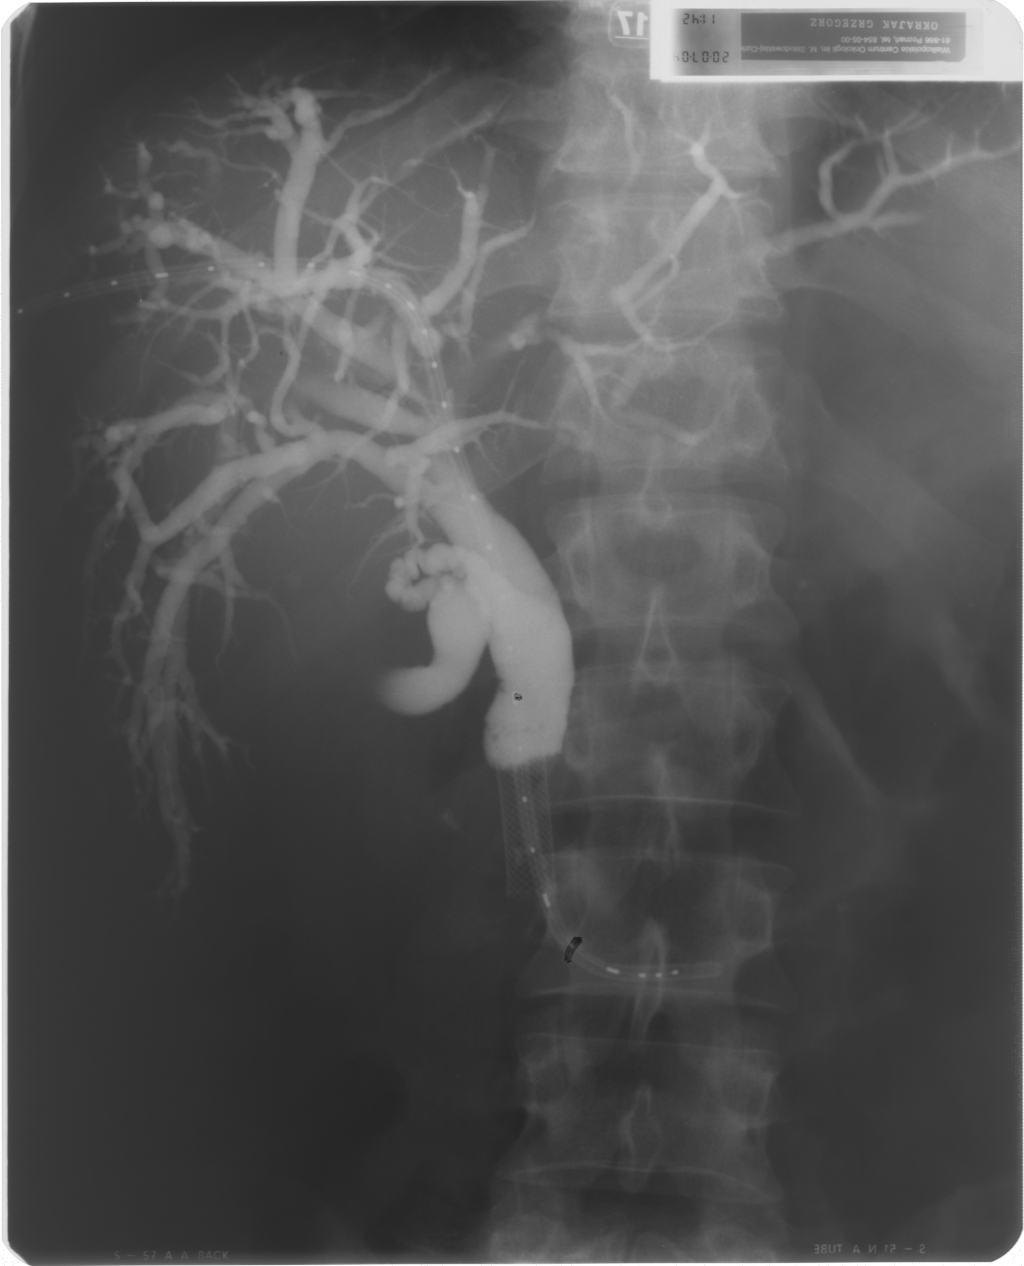

Cholangiografia - widok dróg żółciowych po implantacji aplikatora (French 5) do brachyterapii, założono dren 10 F metodą rendez-vous, widoczny stent